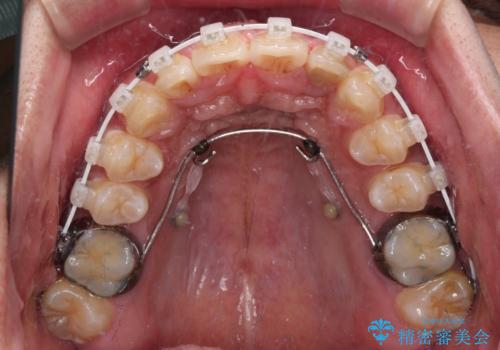

抜歯は行わず、補助装置を用いて上顎歯列全体を後方移動させ、ワイヤー装置にて奥歯の咬み合わせを改善していくこととしました。

正面や横から見た印象が同じで用であっても、奥歯の咬み合わせが理想的であるかどうかによって、治療の難易度は大きく異なります。

こちらの方も難易度のやや高い状態で、2年以上の期間が予想されましたが、想定通りの2年強で治療を終えることができました。